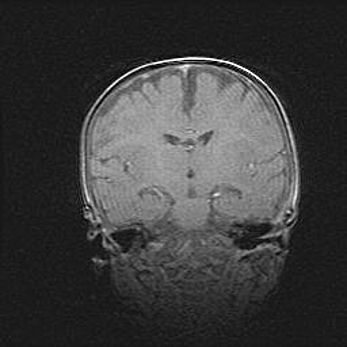

Церебральная ишемия II.

Возраст: 5 дней

Вес: 3400 г

Пол: женский

Окружность головы: 35 см

Срок гестации: 39 недель

Церебральная ишемия – это заболевание, характеризующееся недостаточностью (гипоксией) либо полным прекращением (аноксией) снабжения мозга кислородом по причине закупорки одного или нескольких сосудов. Это приводит к  что метаболическим расстройствам различной степени тяжести в тканях головного мозга, развитию коагуляционных некрозов и гибели нейронов.